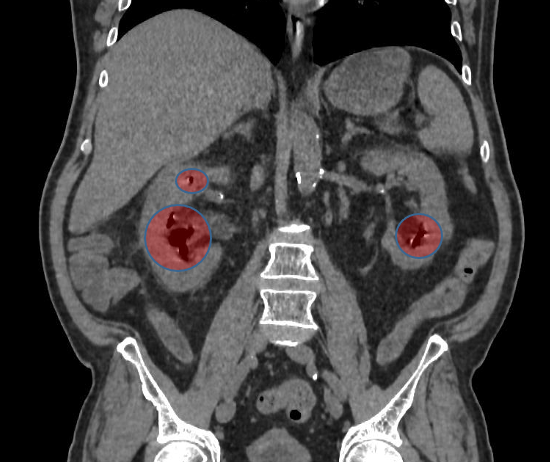

При КТ-обследовании (врач-рентгенолог Горохова Анна Сергеевна) диагностирован эмфизематозный пиелонефрит наиболее тяжелой формы — IV класса.

Компьютерная томография пациента. Обозначены скопления газа в собирательной системе

и паренхиме правой и левой почек.